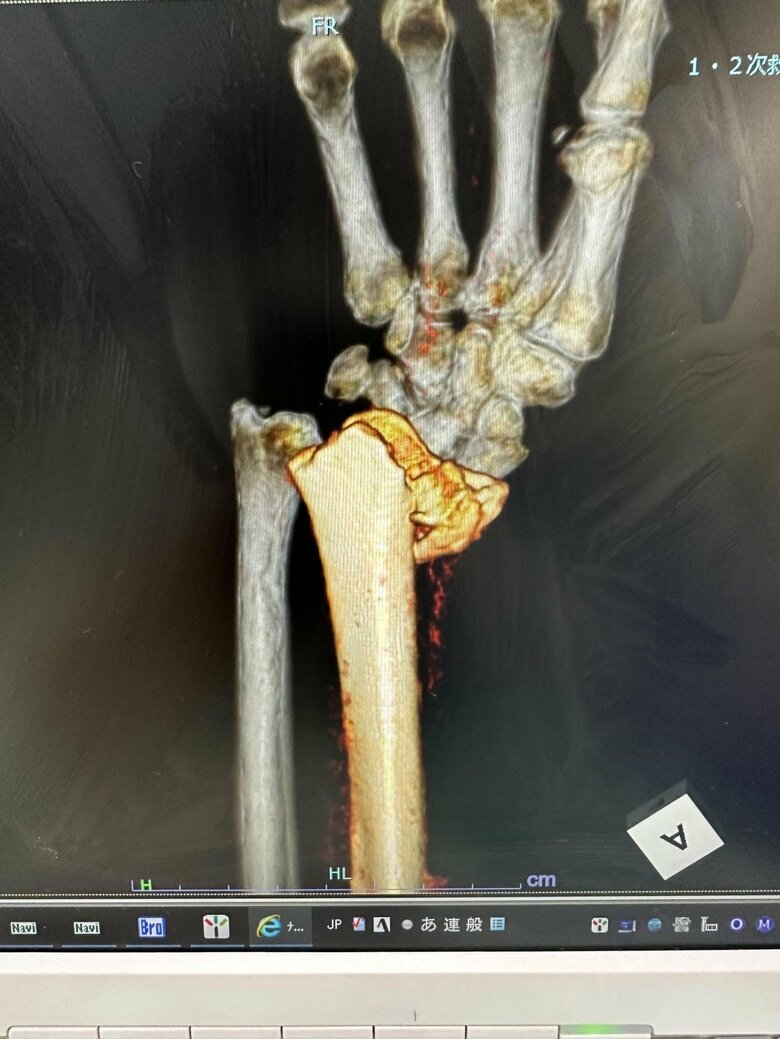

腕をケガし、ズレた骨を元の位置に戻すため器具を装着。この器具を外した後に2度目の手術でプレートをいれ10本のネジでとめた

21/22